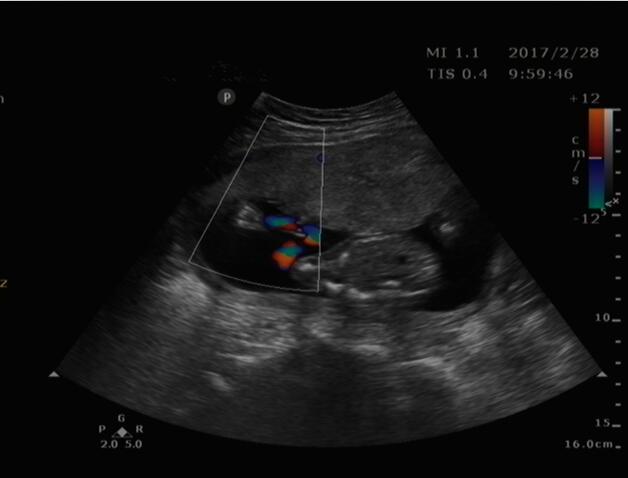

近日,家住商河怀孕4个月的某女士,来我院超声科就诊。接诊大夫为其认真仔细检查,发现该患儿双顶径小于孕周,形态不规则,呈“柠檬头征”,后发现顶枕部一囊性包块,其内含部分脑组织结构,膨出于颅骨外,胎儿其它肢体结构未发现异常。经沟通,此前该女士未做过其它任何检查。随后,该女士在我院办理住院,引产后已证实超声诊断。再进一步了解中得知已孕育两个孩子,其一患有脑积水。

1、头颅中线位置颅骨壁缺损。

2、缺损处突出一包块,脑膜膨出突出内容物为脑膜,膨出物为囊性肿物,脑膜脑膨出突出内容物为脑膜几脑组织,膨出物为实性回声。

3、大量脑组织膨出时颅骨光环缩小或不规则,双顶径可能偏小。